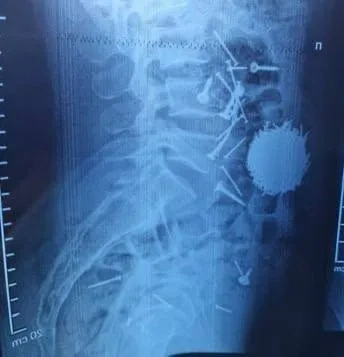

Lent.az xarici mediaya istinadla xəbər verir ki, Səmərqənddə 29 yaşlı kişi təcili əməliyyat olunub. Əməliyyat həkimlərin onun mədəsində ümumi çəkisi 200 qram olan təxminən 100 mismar və vint aşkar etməsindən sonra baş tutub.

Həkimlərin sözlərinə görə, kişi ağır stress altında olub və hərəkətlərini idarə edə bilməyib.

"Əməliyyat uğurlu keçib və vəziyyəti hazırda stabildir", - məlumatda bildirilir.